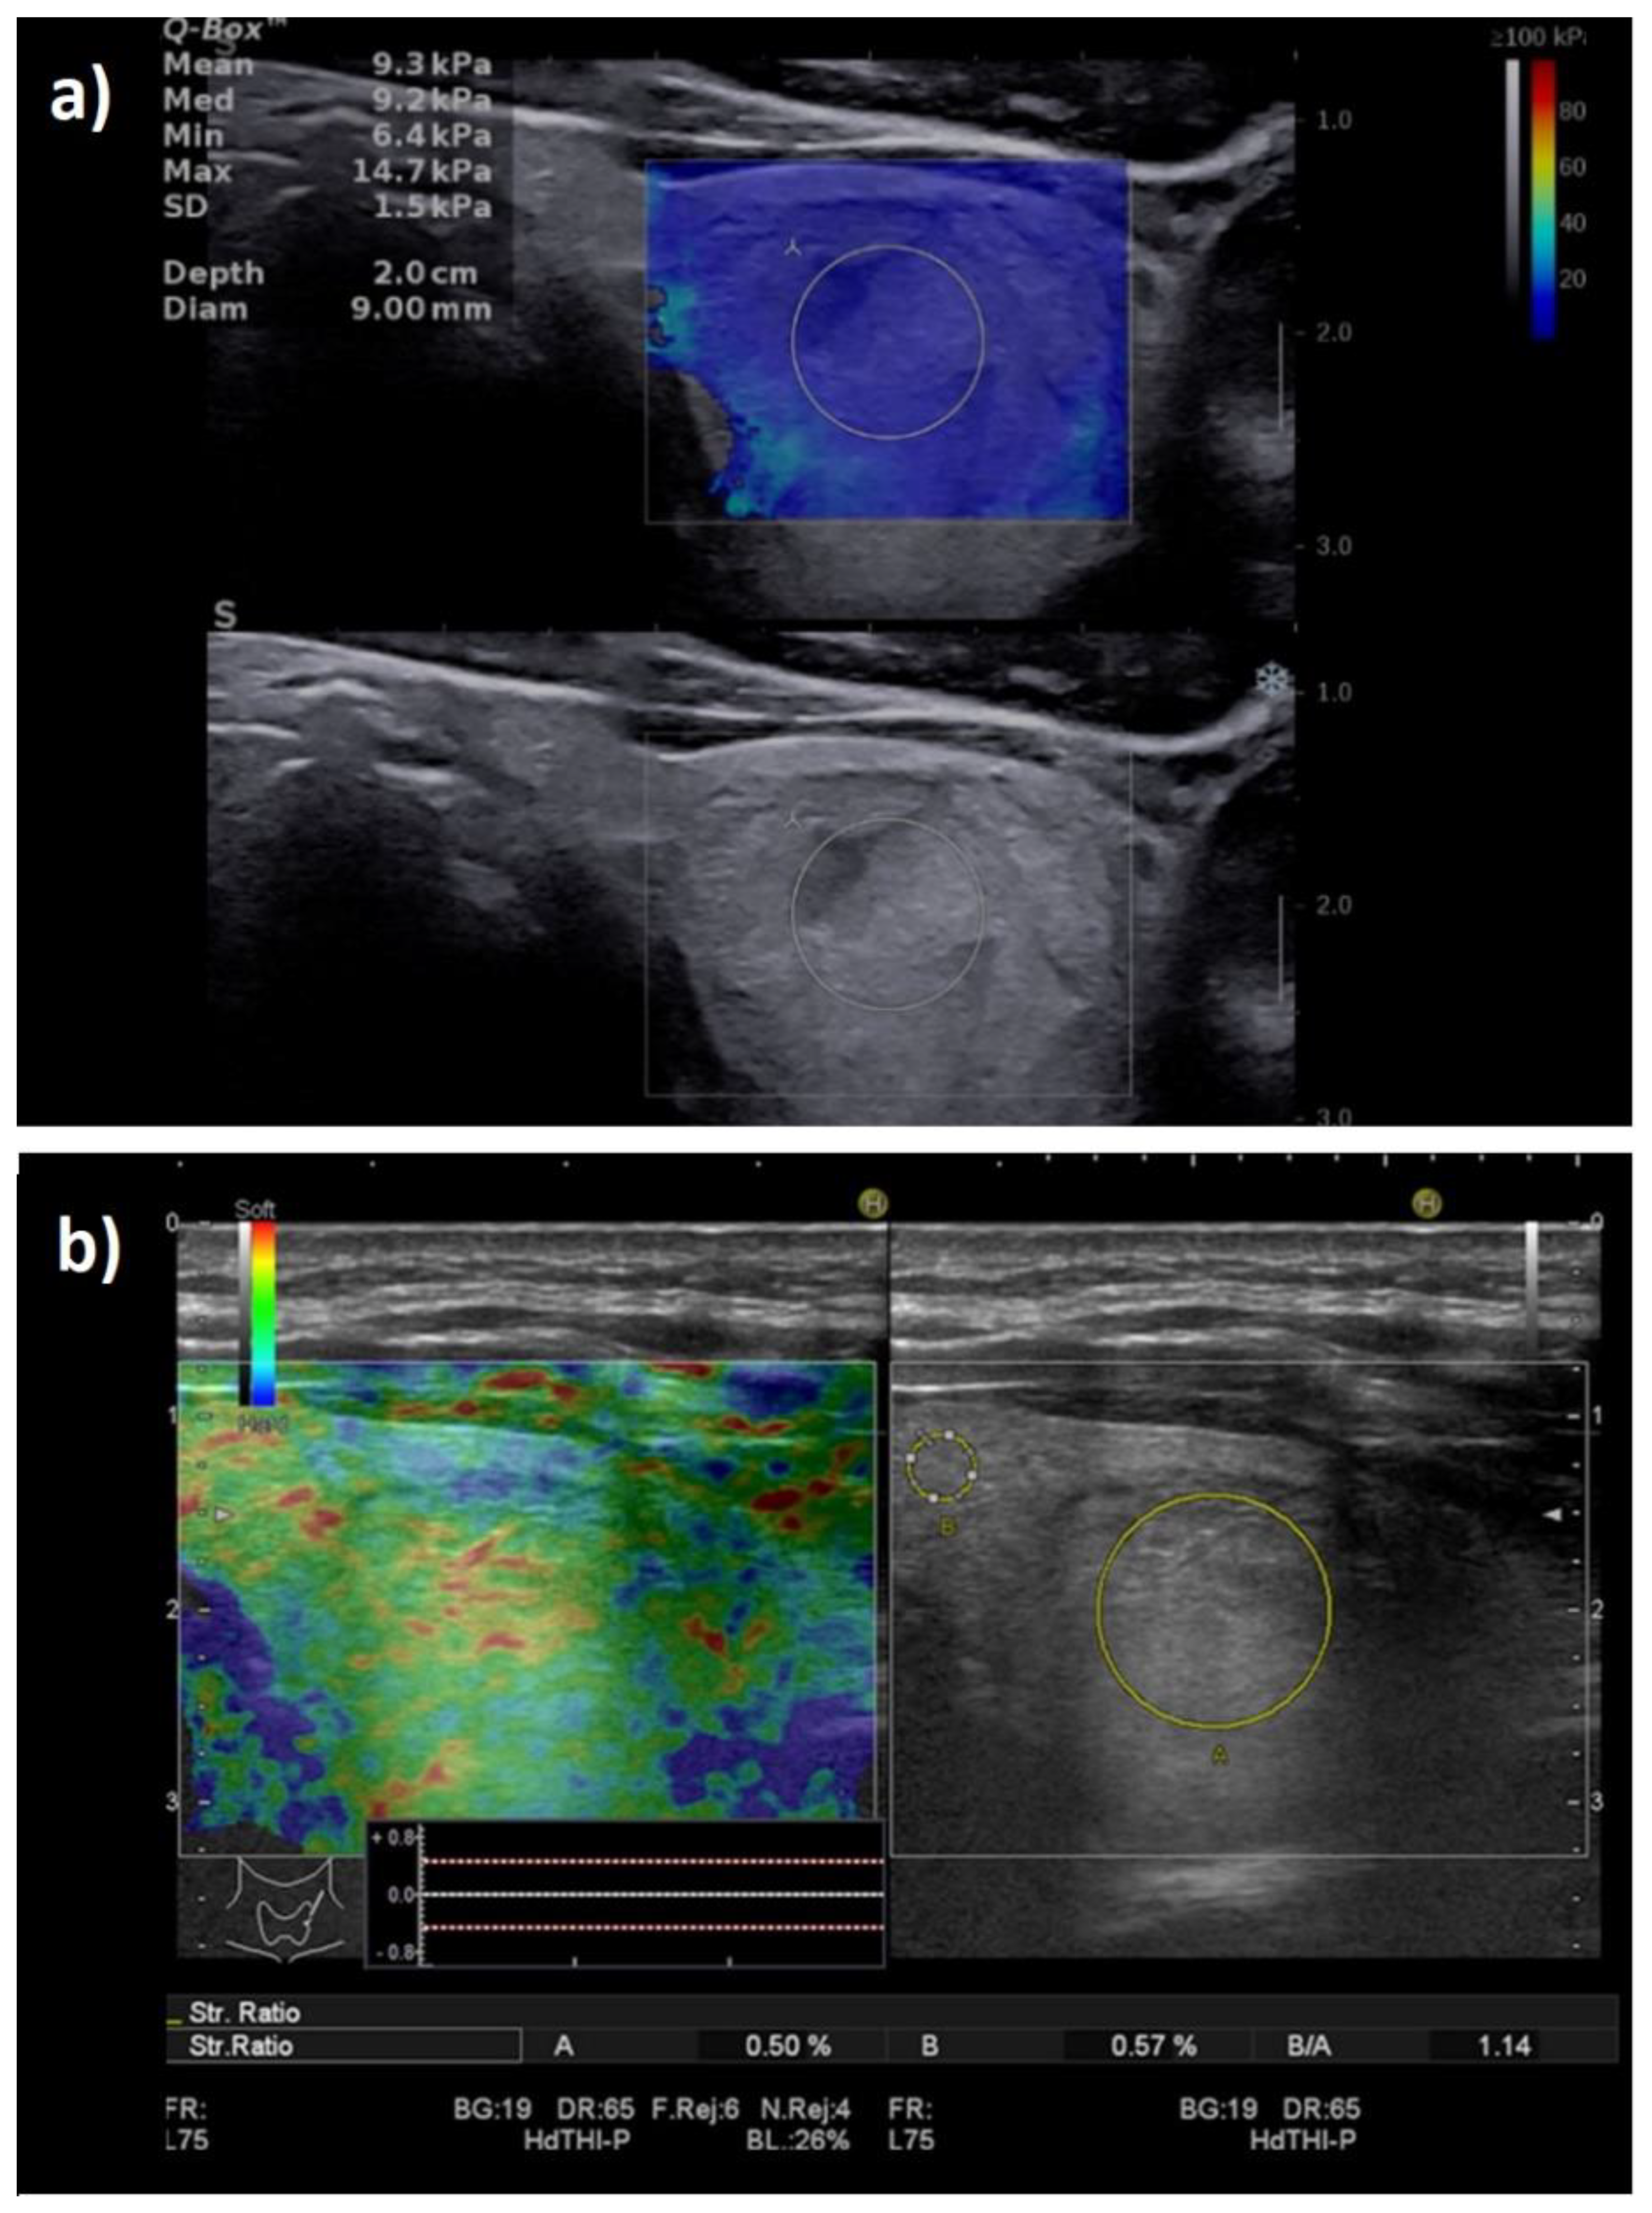

Four benign lesions were hard according to the SWE evaluation and were included in the high-risk category. One of them was also stiff in SE, corresponding to a case of Riedel thyroiditis that was misinterpreted as a high-risk focal lesion (see Figure 10); the false positives in SWE were two follicular adenomas.

Figure 10.

Illustration of false-positive elastography results in a case with Riedel thyroiditis. Appearance of hypoechoic thyroid nodule, with increased stiffness both in (a) shear-wave elastography: Mean elasticity index = 64.3 kPa; and in (b) strain elastography: entirely stiff nodule (entirely blue), Asteria score of 4 and strain ratio = 5.5.

Six benign lesions presented increased stiffness in SE. One case, the above-mentioned Riedel thyroiditis, was in agreement with SWE; the other five cases (four follicular adenomas and one nodule in lymphocytic thyroiditis) were “soft” in the SWE examination.